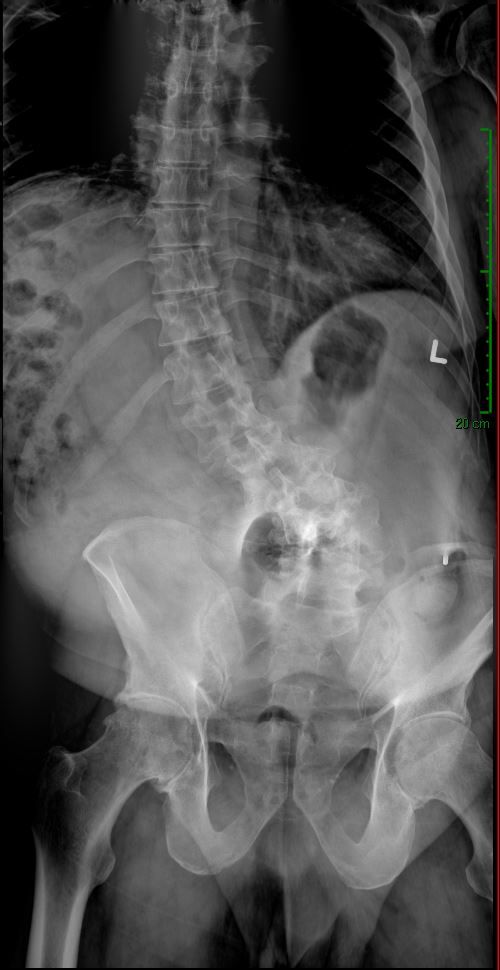

De-identified imaging from complex spine surgery cases. Each pair shows pre-operative pathology alongside post-operative correction across cervical, lumbar and deformity subspecialties.